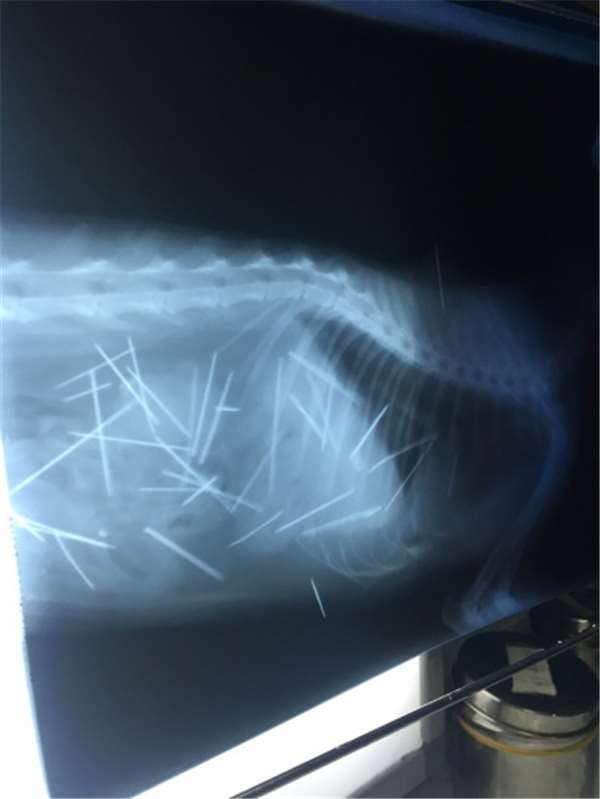

事情發生在中國深圳,5月19日暱稱為Annie的網友急忙上微博求助,她稱家裡有隻收養了一年的貓咪,最近摸貓的脖子後面發現有突起,多貓幾下貓咪有明顯的痛感,帶去獸醫院照X光才發現,貓的體內居然有30~40根針!

密密麻麻的針令人怵目驚心,微博立刻有三萬人次的轉發。

獸醫表示,7根針是在皮膚或肌肉,3根針和2個斷端在胸腔心臟旁邊。30根針在腹腔,其中有4根是插入到左側腎臟。這是一個複雜的手術。

為了手術順利進行,這個可憐的橘貓,X光連續照了53次。

經過40小時的漫長手術,終於取出了43根針裡頭包含斷掉的針,許多針已在體內生鏽。